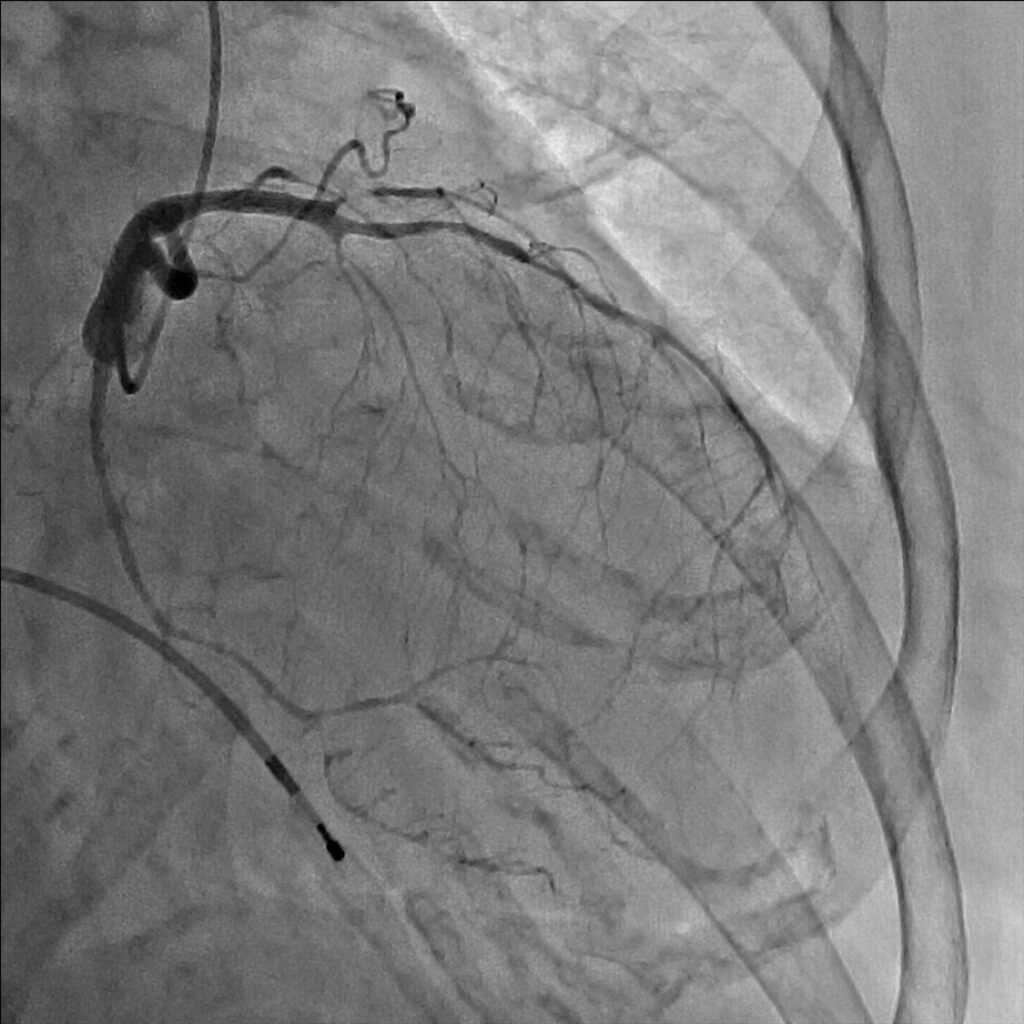

安静時狭心症の診断には、労作性狭心症にもまして詳細な症状の聴取が重要です。専門医が症状を詳細に聴取することで、ほぼ100%の診断が可能と言われています。疑わしい場合は、発作時にニトロペンの舌下使用を試し、著効するか否かで診断することもできます。カテーテルを使った冠動脈造影時に、アセチルコリンという薬剤を用いた冠動脈攣縮誘発試験で冠攣縮の有無を判定することが一般的です。

冠動脈の狭窄が急激に進行するために生じると考えられています。その原因は冠動脈の壁の中にできたコレステロールの塊(粥腫)が破れ、その部に血栓(血液の塊)が生じるためです。冠動脈造影検査をすると、多くの場合、血栓により冠動脈腔がほぼ閉塞状態であることが確認されます。